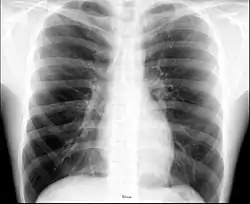

The major pathophysiologies encountered in blunt chest trauma involve derangements in the flow of air, blood, or both in combination. Sepsis due to leakage of alimentary tract contents, as in esophageal perforations, also must be considered. Blunt trauma commonly results in chest wall injuries (e.g., rib fractures). The pain associated with these injuries can make breathing difficult, and this may compromise ventilation. Direct lung injuries, such as pulmonary contusions (see the image below), are frequently associated with major chest trauma and may impair ventilation by a similar mechanism.